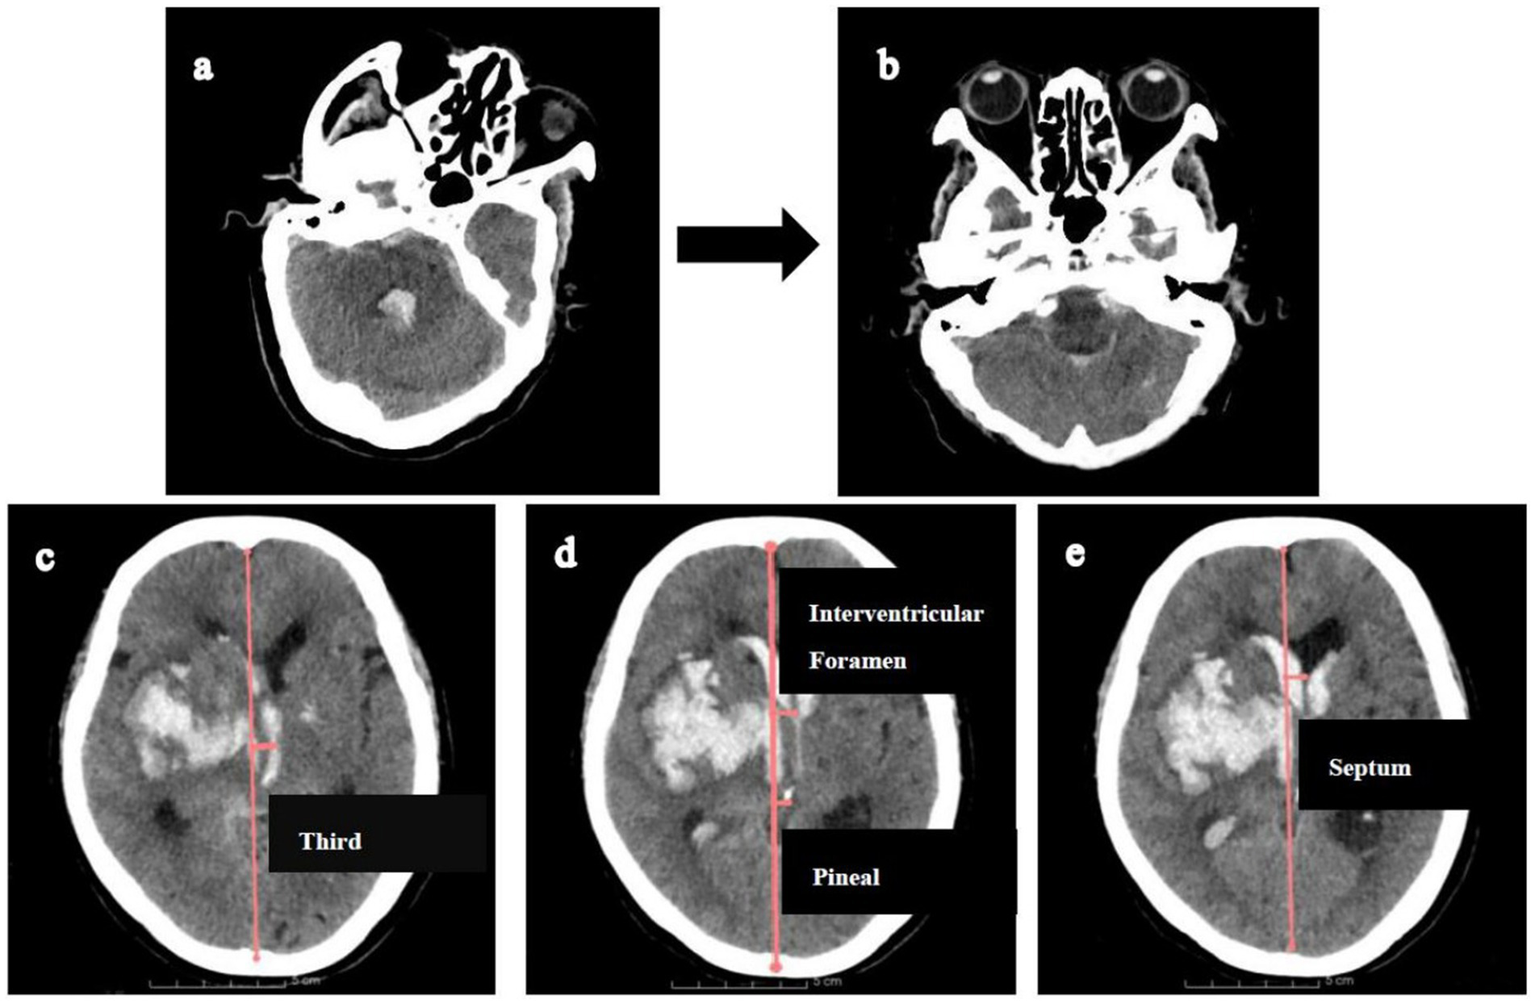

This study adhered to the Declaration of Helsinki and was approved by the Research Ethics Committee of the Affiliated Hospital of Shandong Second Medical University (wyfy-2024-ky-173). Informed consent was obtained from all participants or legal guardians. One patient provided permission to display their CT scan demonstrating location-specific midline shifts (Figure 2).

Figure 2

Illustration of measuring midline shifts (MLS) at various levels. Firstly, CT reconstructions (a,b) were aligned with the orbitomeatal line to facilitate accurate midline shift measurements. Then, MLS was quantified by constructing an ideal midline (red line), linking the most anterior and posterior visible points on the falx. (c). MLS at the level of third ventricle. (d) MLS at the level of interventricular foramen and pineal gland. (e) MLS at the level of septum pellucidum.

Midline shift quantification adhered to this protocol: (1) CT reorientation: Alignment to the orbitomeatal plane via rigid transformations (Transforms module); (2) Midline definition: an ideal midline (iML) construction connecting anterior/posterior falx cerebri dural insertions; (3) Displacement measurement: Perpendicular distances from iML recorded at: pineal gland, third ventricle, foramen of Monro, and septum pellucidum (Figure 2).